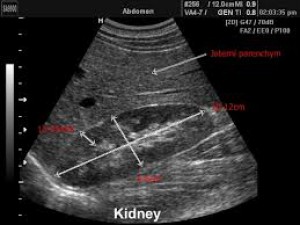

USG obličiek hlavne u nemočiacich pacientov je základné nenáročné vyšetrenie. Veľmi jednoducho kedykoľvek realizovateľné aj priamo na oddelení, napríklad INT - respektíve všade tam, kde je USG prístroj k dispozícii.

Stačí priložiť sondu na lumbálnu oblasť a odlíšiť fyziologický prierez obličky od hydronefrotického - čo nemôže byť problém. Okamžite zistíte či potrebujete nefrológa, alebo urológa.